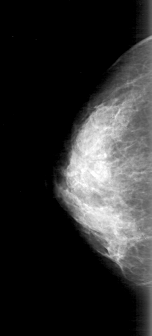

D_4168_1.RIGHT_CC

FILE: D_4168_1.LEFT_CC.OVERLAY

TOTAL_ABNORMALITIES 1

ABNORMALITY 1

LESION_TYPE CALCIFICATION TYPE AMORPHOUS DISTRIBUTION SEGMENTAL

ASSESSMENT 0

SUBTLETY 4

PATHOLOGY BENIGN

TOTAL_OUTLINES 1

BOUNDARY